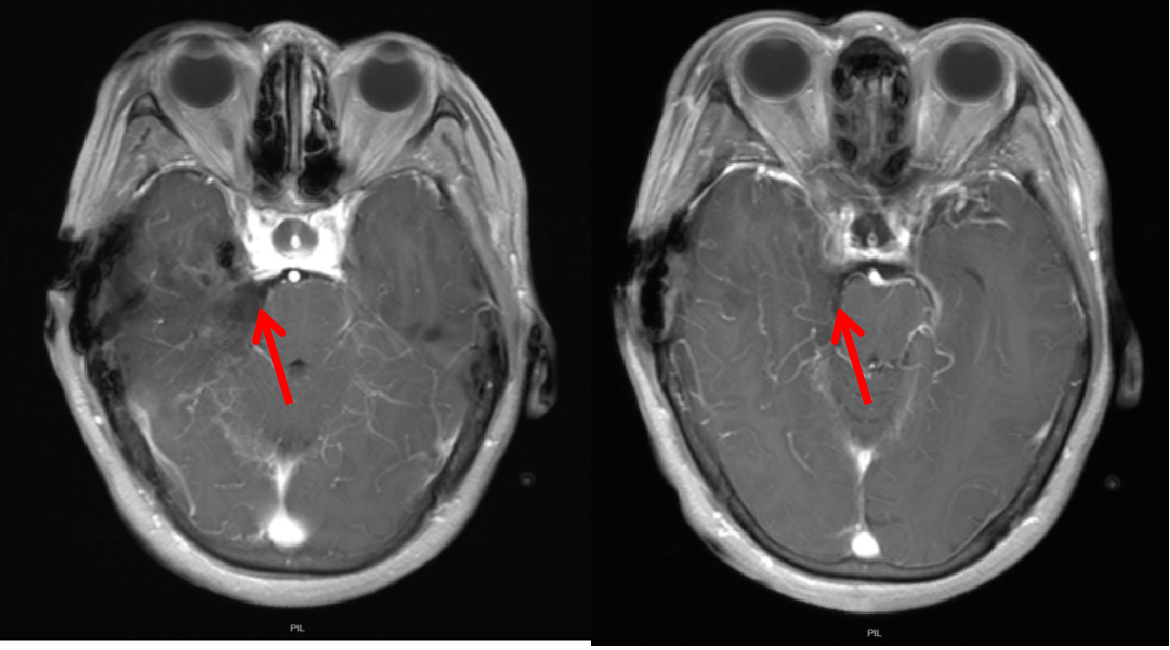

术前磁共振弥散

术后磁共振弥散示肿瘤切除较完全